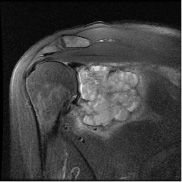

Kıkırdak hücresi üreten kötü huylu bir tümördür. En sık 30-60 yaş arasında görülür. Sıklıkla femurun (uyluk kemiği) her iki ucunda, humerusun (kol kemiği) üst ucunda, pelvis (leğen kemiği), kaburga, omurga ve kafa kemiklerinde görülebilir. Kondrosarkomlar primer ve sekonder olmak üzere iki gruba ayrılır. Elde nadir görülmesine karşın malign el tümörleri içerisinde üst sıradadır.

Doğrudan kemik ve yumuşak dokudan çıkanlara primer kondrosarkom denir. Daha önce var olan osteokondrom veya enkondromdan çıkanlara sekonder kondrosarkom denir. Kondrosarkomların %75’i primer, %25’i sekonderdir.

BT; kemik periostundaki değişiklikleri, kortikal değişiklikleri, kitle içindeki kalsifikasyon ve patolojik kırıkları gösterebilir.

MRI ise kemik medullasındaki tutulumu, yumuşak doku komponentini, damar sinir ilişkisini, eklem tutulumunu ve skip metastazı en iyi gösteren görüntüleme yöntemidir.

1. Klasik Medüller Kondrosarkom

Sıklıkla pelvis (leğen kemiği), femurun (uyluk kemiği) ve humerusun (kol kemiğinin) üst ucunu tutar. Kondrosarkomların %80’nini oluşturur. 30 yaş üzerinde sık görülür. Grade I kondrosarkomlarda lezyon içerisine girilerek geniş küretaj yapılır. Grade II ve üzeri lezyonlarda lezyon için cerrahi girişimlerde lokal nüks riski çok yüksektir. Bu tip kondrosarkomlarda mutlaka geniş sınırlar ile rezeksiyon yapılmalıdır. Histolojik derece çok yüksek ise kemoterapi eklenebilir.